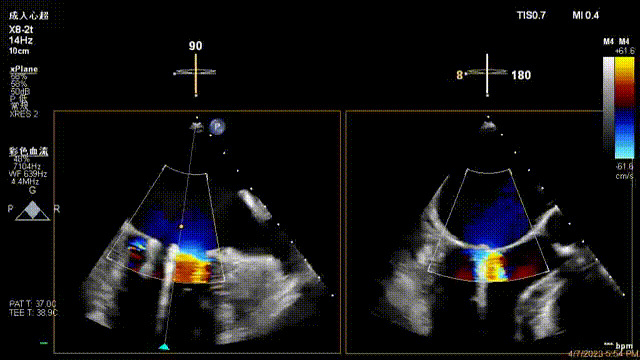

術(shù)后超聲顯示二尖瓣反流消失,瓣膜夾穩(wěn)定